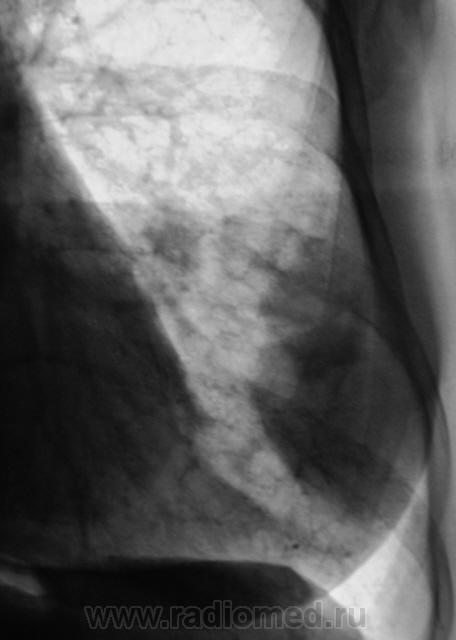

Контроль после флюорографии. Стандартное дообследование.

Ваше мнение уважаемые коллеги?

Mts? Но откуда? Что в анамнезе?